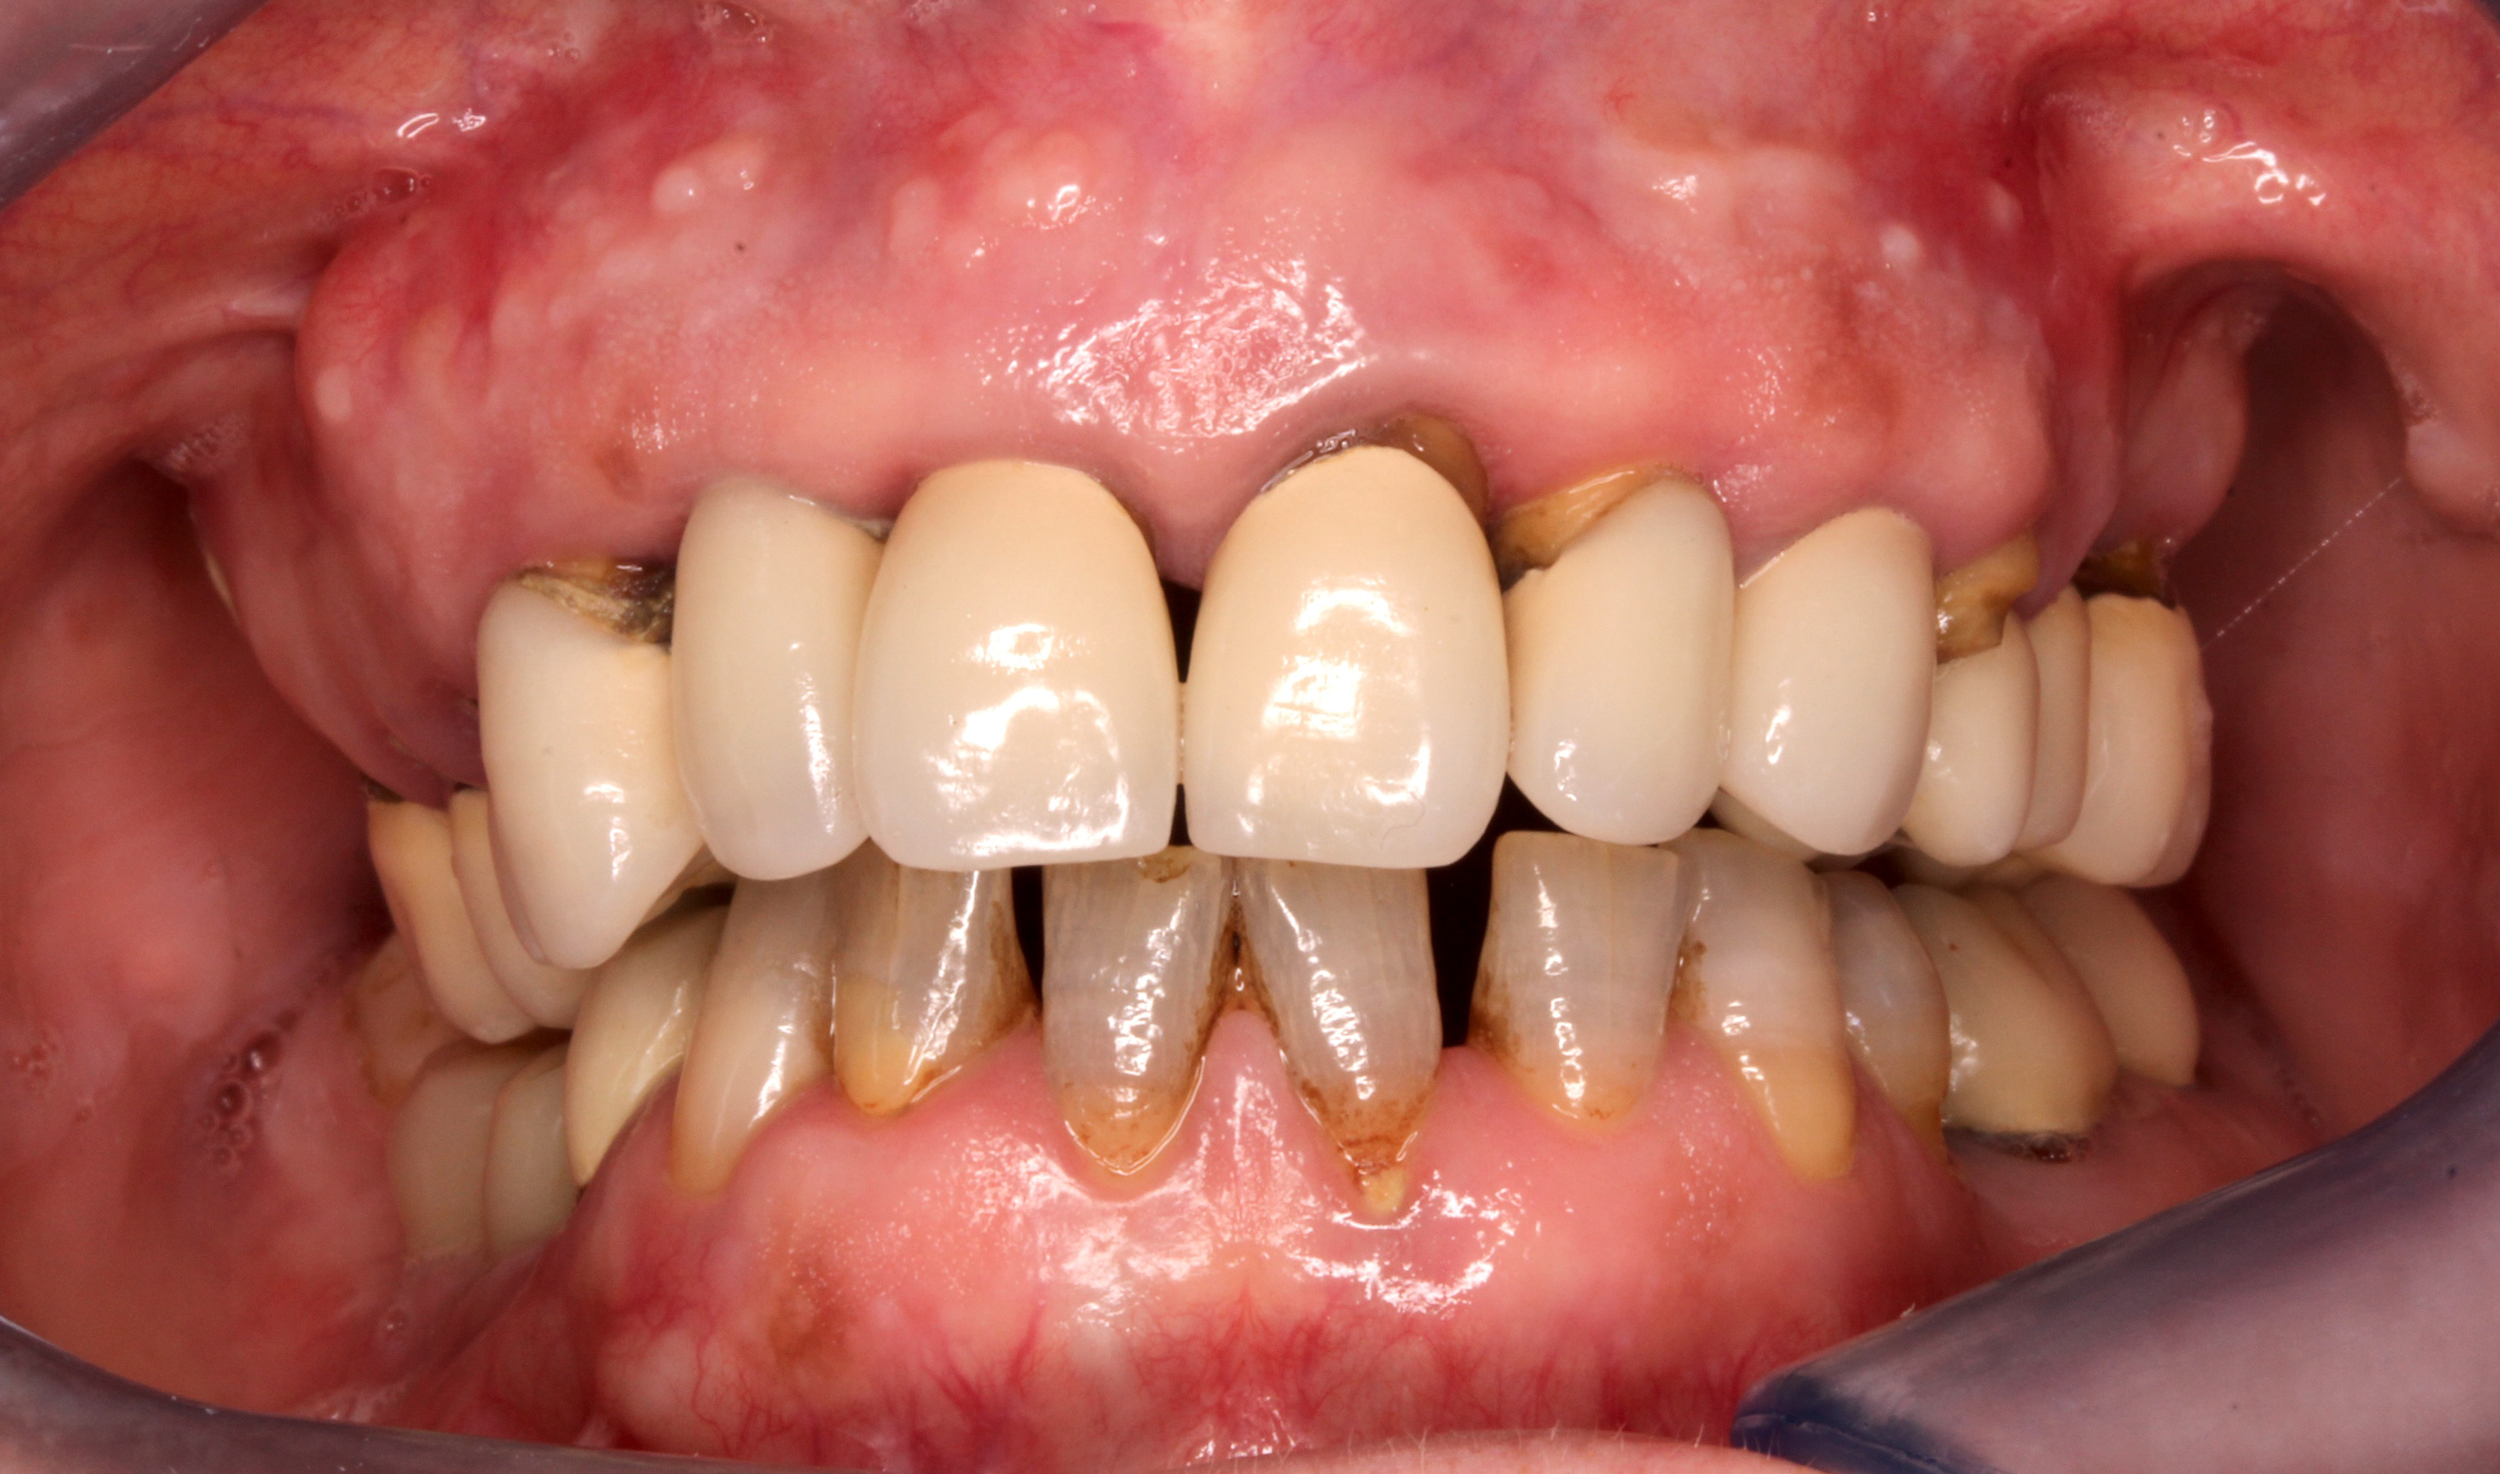

Riabilitazioni complesse con mantenimento

dei denti naturali

In alcune situazioni, anche quando è necessario inserire più impianti, è possibile preservare i denti naturali presenti e valorizzarli con altri trattamenti come ortodonzia, faccette, corone o innesti gengivali. Questo approccio permette di combinare diverse tecniche per ottenere un risultato finale armonioso, funzionale e naturale, rispettando al massimo la struttura dentaria residua.

Caso 3 - Caso 4

PRIMA

DOPO